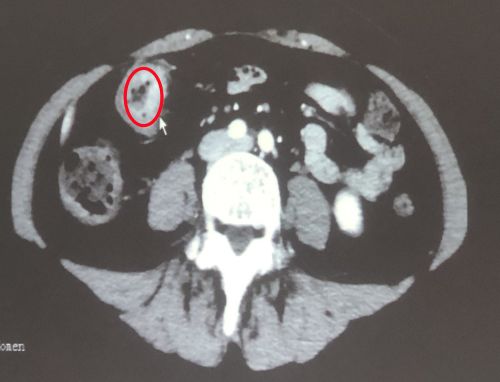

治疗前影像显示:肠道内有肿瘤(红圈内)。